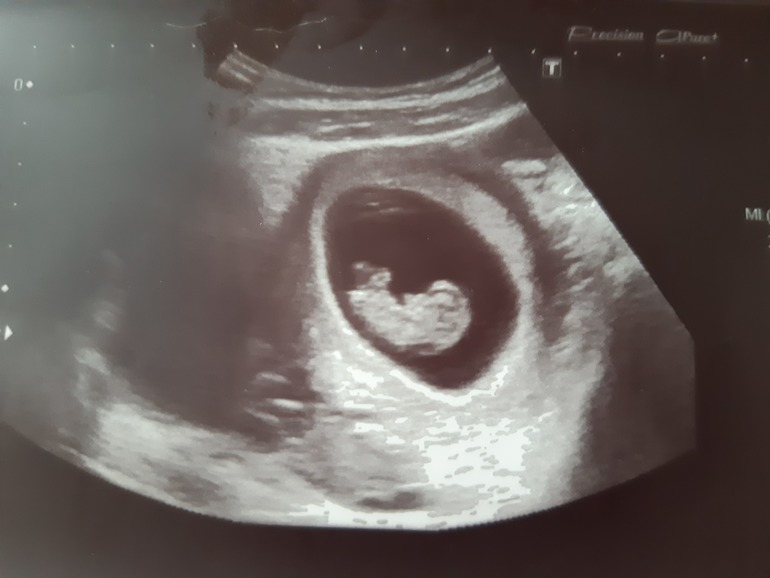

9+3 недель, узи

Ого, уже ручкой махал! Фоточку покажите))

Ну не знаю где муж с врачем увидели там ручку...))))но говорят, что было)

Что-то похожее на ручку угадывается)) А вообще на экране все так хорошо видно! А фотки дают - одна размазня. Даже на более поздних сроках ничего ни различить. Еще девчонки там как-то пол угадывают по таким фоткам. Я ничего не вижу))

Какой уже большой) прям человек человек)